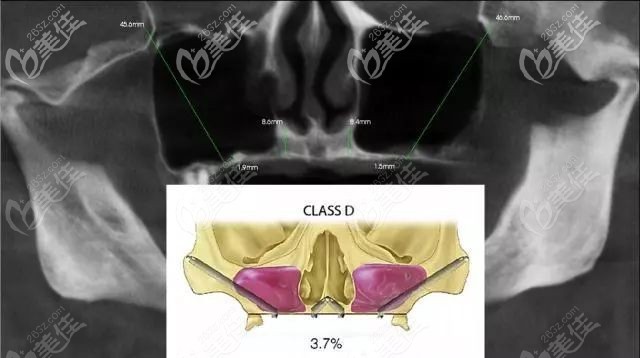

举例:顾客术前口腔的评估结果▲

是通过上颌结节到翼板区的种植统称为上颌翼板区种植,相比传统的种植牙技术,翼板种植技术的优势则在于:

解决了牙槽骨流失“无法种牙”的大难题,翼板种植不需要植骨,牙槽骨极度萎缩的顾客也可以通过翼板受力实现上颌即刻负重,还能保留上颌窦的完整性。